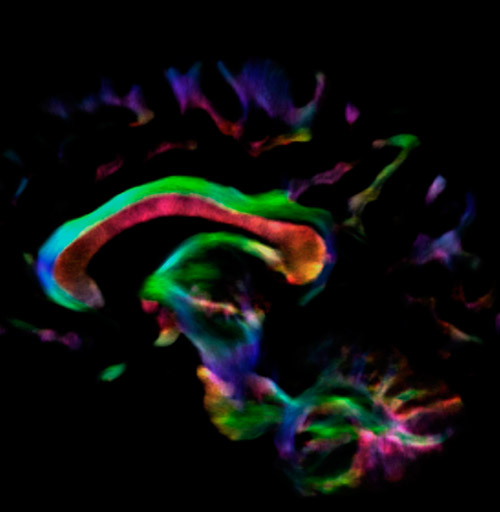

Crossing fibers of the corpus callosum bordered by the superior longitudinal fasciculus as well as within in the pons.

Super-resolution directionally encoded color track-density imaging overlaid on T1-weighted structural MRI.